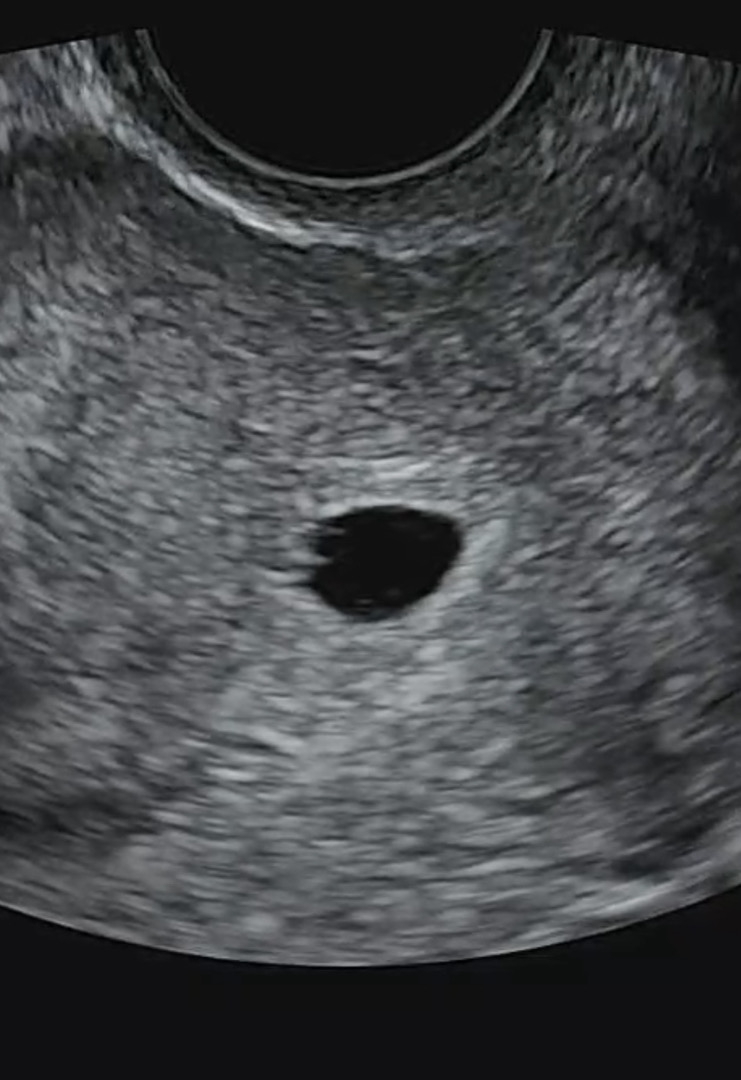

안녕하세요 오늘로 5주6일차 됩니다 저번주에 아기집 확인하고 8일뒤인 오늘 초음파 확인하고 왔는데요 난황이 너무 흐릿하게 보인다고 아직 난황이라고 확실하게도 말씀을 못드린다고 3일 뒤에 초음파로 다시 확인하고 그때도 흐리면 고사난자 인것 같다고하시는데 사실 제가 6월달에 고사난자로 한번 유산경험이 있어서 더 불안 하네요 그때도 6주2일까지 난황이안보여서 수술했었거든요 3일뒤에가면 또 6주2일인데 그때는 진하게 보이길 같이 기도해주시면 감사하겠습니다👶🏻

난황이 흐릿하게보여요 ㅠ